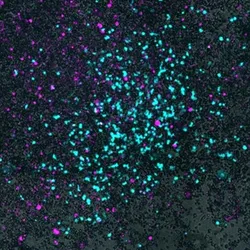

A microscopy image of cyan bacteria cells invade gray lung cancer cells on a black background.